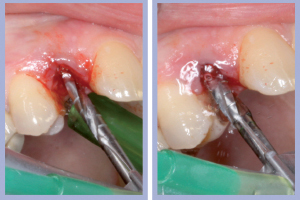

- Figg. 4a, b – Scollamento

- Figg. 5a, b – Estrazione dei canini da latte

- Figg. 6a, b – Estrazione dei canini da latte

- Figg. 7a, b – Toilette chirurgica

- Figg. 8a, b – Mappatura alveolare tramite sonda parodontale